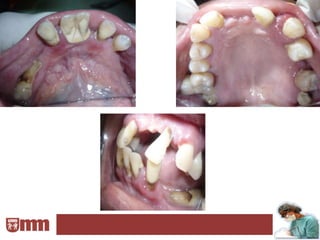

Las prótesis en la boca se pueden apoyar en:

En dientes

Sobre la mucosa         propios del       Sobre implantes

paciente

• Encías             • En forma de       • Podrán ser

• Paladar ( bóveda     ganchos             prótesis fijas

palatina)            (retenedores)     • Y removibles

• Y en forma de

coronas y sus

variantes

(onlay,Tinker,

etc.)

Según el apoyo de la prótesis diremos que son:

Mucosoportadas               Se apoyan exclusivamente sobre la mucosa bucal

Dentosoportadas            Se apoyan en piezas dentarias propias del paciente

Implantosoportadas                  Se apoyan sobre implantes dentarios

Mucodentosoportadas

Se apoyan sobre la mucosa y en los dientes propios del

Mucoimplantosoportadas     Se apoyan sobre la mucosa bucal e implantes dentarios

Dentoimplantosoportadas

Se apoyan en dientes del paciente y en implantes

dentarios.